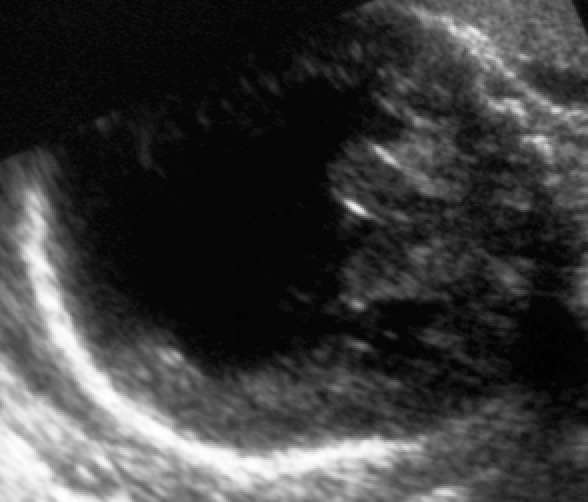

Dysmorphic baby

Diagnosis?

Holoprosencephaly

(often associated with missing nose, single eye, and other midface abnormalities)

Large monoventricle, fused thalami, absence of falx